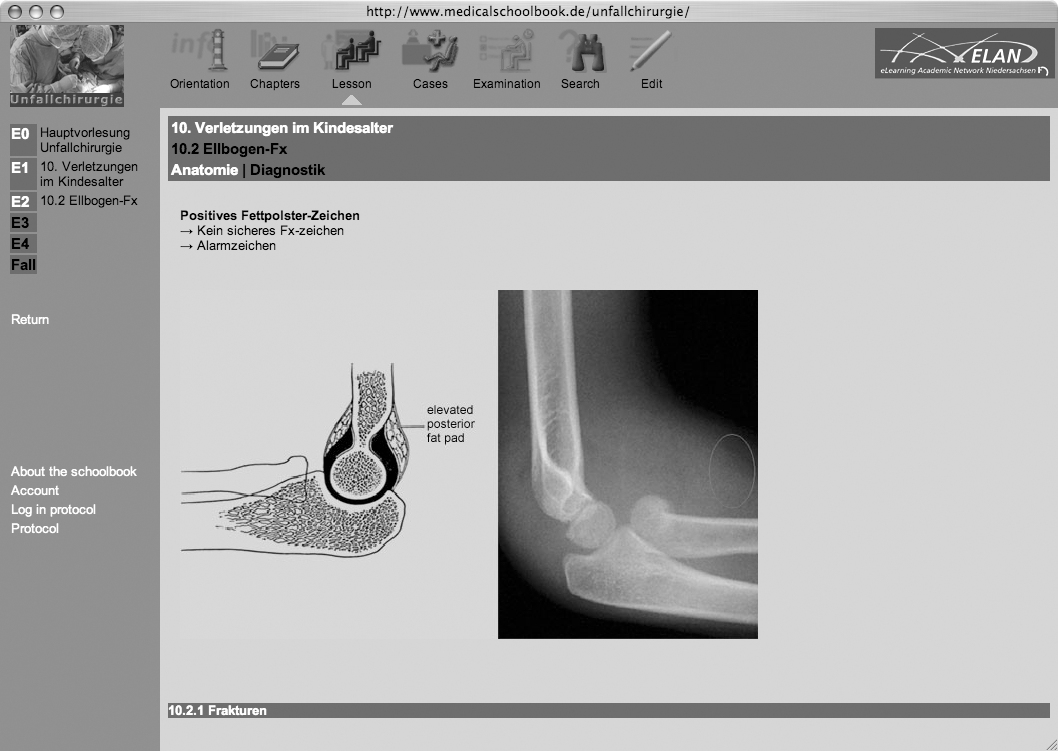

Das Unfallchirurgie-Schoolbook (Abbildung 1 [Abb. 1]) wurde in allen drei Tertialen des Studienjahrs 2005/06 im Blockpraktikum Chirurgie (Abbildung 2 [Abb. 2]) eingesetzt. Evaluiert wurden zunächst die ersten beiden Tertiale. Der Einsatz des Schoolbooks kann nach den vorhandenen Evaluationsergebnissen (Tabelle 1 [Tab. 1] und Abbildung 3 [Abb. 3]) als sehr erfolgreich gewertet werden. Die Studierenden haben großes Interesse an Online-Angeboten, die sie in erster Linie zu Hause nutzen. Ein großer Teil der Studierenden verfügt zu Hause bereits über gute Internetverbindungen. Weiterhin zeigte sich, dass das Schoolbook zu einer intensiveren Auseinandersetzung mit der Unfallchirurgie führte, wodurch eine langfristige Lernbereitschaft erreicht werden kann. Die Möglichkeit die Vorlesungen nachzuarbeiten wird von den Studierenden sehr positiv bewertet, ohne dass dadurch die Anwesenheit bei Vorlesungen als unwichtig betrachtet wird. Vielmehr führt die Möglichkeit die Vorlesung mit Hilfe des Schoolbooks vor- und nachzubereiten eher zu einer „besseren Konzentration auf die Vorlesung“ (studentischer Kommentar bei Evaluation). Die Verwendung von eLearning-Modulen innerhalb der Vorlesung erhöht weiterhin entscheidend dessen Akzeptanz bei den Studierenden.

Abbildung 1: Screenshot vom Unfallchirurgie-Schoolbook